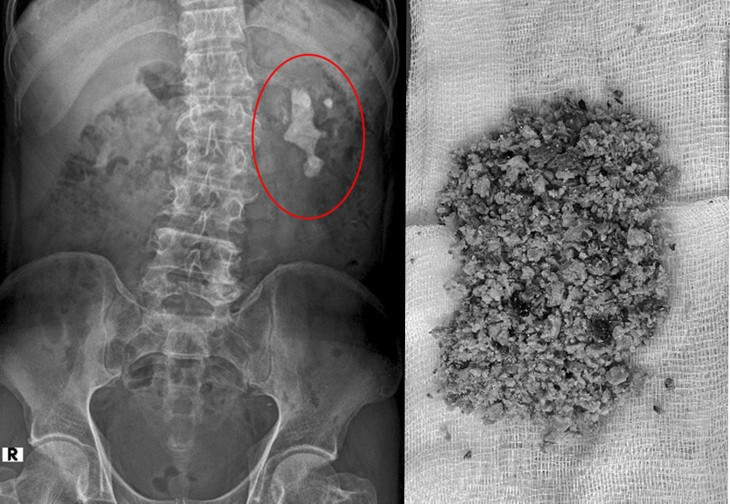

![]() |

| Sỏi thận trên phim chụp và được lấy ra - Ảnh BVCC |